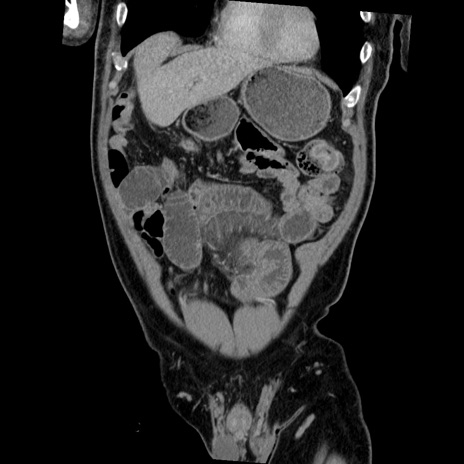

症例22(冠状断像)

【症例】50歳代男性

【主訴】腹痛

【現病歴】AVMからの被殻出血のため回復期リハ病棟入院中。 本日午後3時頃急に下腹部痛が出現した。

【既往歴】AVM、被殻出血、虫垂炎、高血圧

【身体所見】意識晴明、左半身不全麻痺、会話の理解は良好、36.5°C、腹部:膨隆、全体に板状硬、下腹部正中に圧痛点あり、反跳痛-、筋性防御不明、右下腹部にope scar

【データ】WBC 9400、CRP 0.06